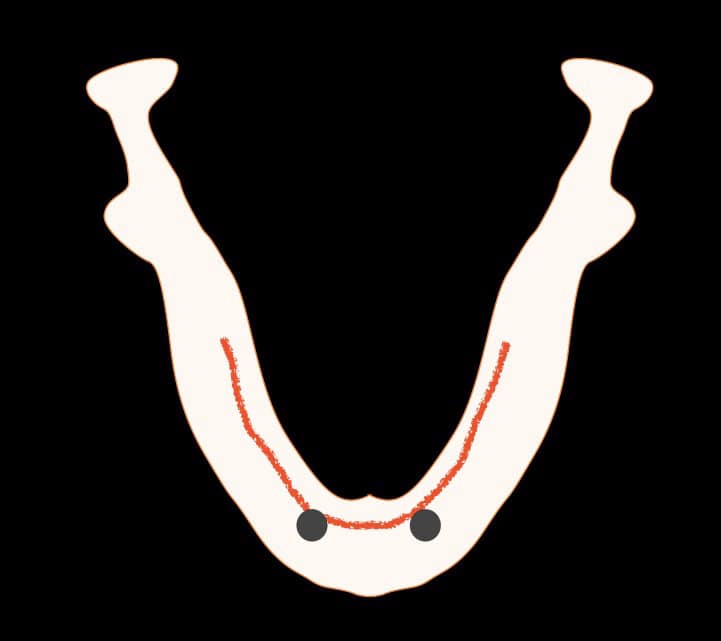

The bone resorption pattern in the edentulous mandible often results in the mucogingival line to be transposed rather lingual. This means that the bulk of the volume of the mandibular bone is under the mobile oral mucosa, rather than the keratinised. Due to possibly the local anatomic characteristics but also the removable nature of the overdenture, lack of keratinised mucosa in such cases can increase the risk for inflammation and difficult to resolve problems of the soft tissues. In such cases I would recommend preventive increase of the keratinised mucosa width in the position where the implants will be placed